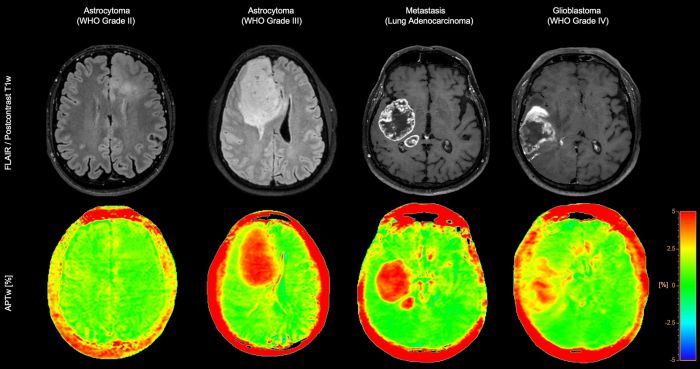

Діагностична впевненість у нейроонкології

3D APT (Amide Proton Transfer) – унікальний метод МРТ-візуалізації головного мозку без використання контрасту.

Він використовує наявність ендогенних клітинних білків для створення МР-сигналу, що безпосередньо корелює з проліферацією клітин – важливим індикатором пухлинної активності.

3D APT підвищує діагностичну впевненість при нейроонкологічних дослідженнях.